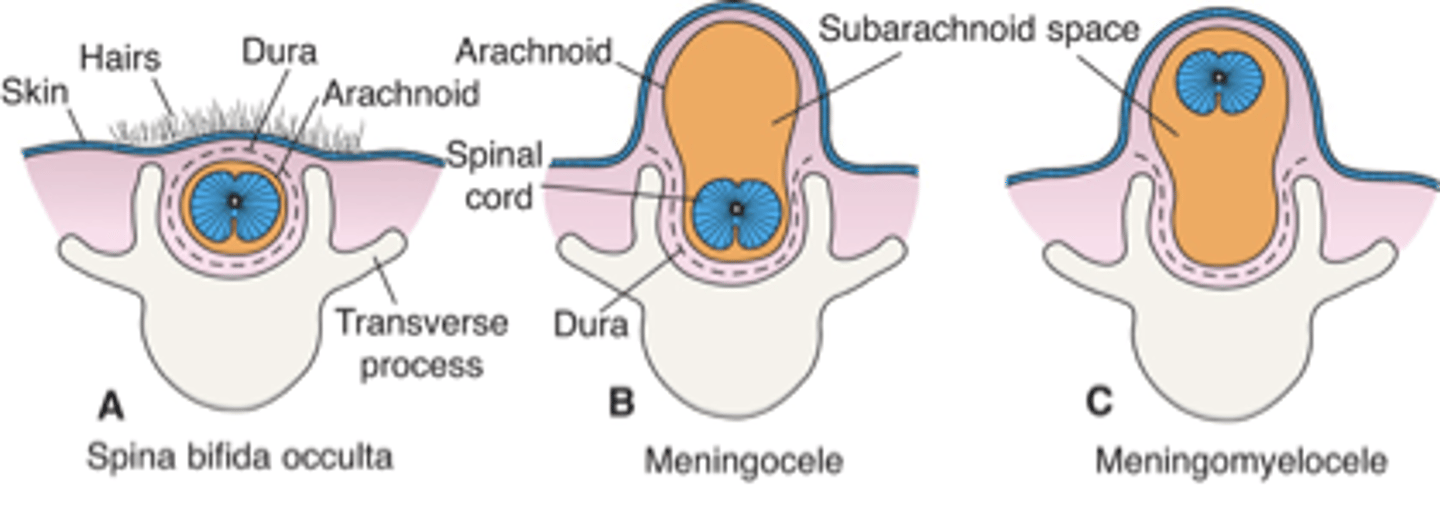

what neural tube defect is caused by the failure of the caudal neuropore to close and varies in severity (like meningocele and myelomeningocele)?

spina bifida